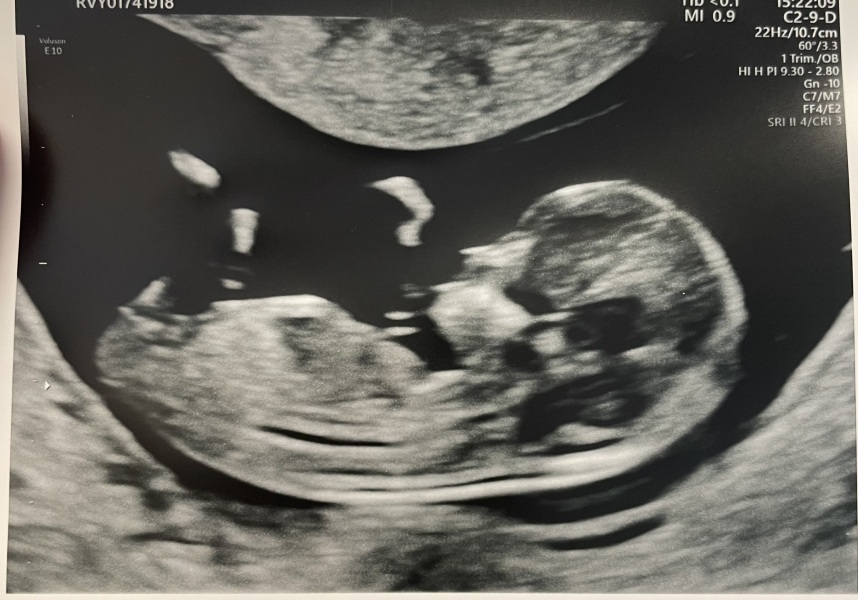

Scan showing 12 weeks and 1 day. It is difficult to see the nub. What are people’s thoughts? I’ve had such a mixture of opinions with lots saying boy, some saying girl and a few saying there’s no nub in the picture. I’d love a girl after two boys as this is my last but it’s looking unlikely.